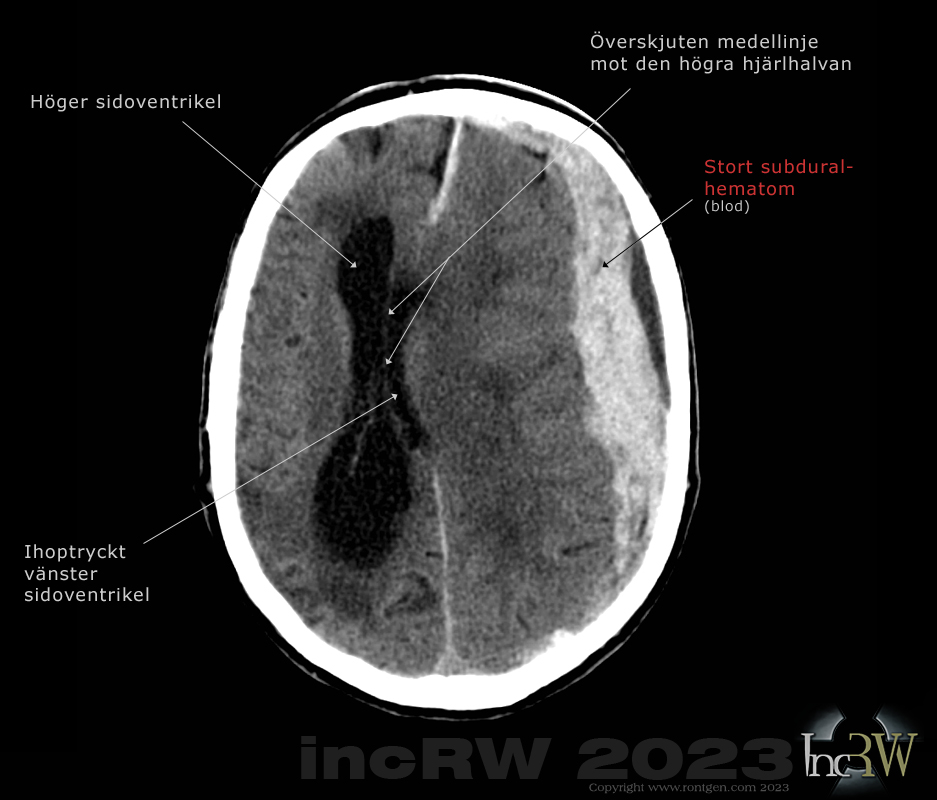

Subdurala hematom är oftast venösa blödningar innanför skallbenet som uppkommer efter trauma (kontusion) mot skallen.

Misstanke på subduralhematom följs oftast upp oavsett om diagnosen är tydlig eller man vill följa hematomets utveckling dvs. om den växer på sig eller avstannar efter en kort tid.

Man gör således ofta om denna CT-undersökning efter 1-3 dagar och sedan under några veckor för att kontrollera att blödningen inte fortsätter att fylla på utrymmet mellan de yttre hjärnhinnorna och då ev. ger en förskjutning av hjärnans medellinje (medellinjsdislokation).